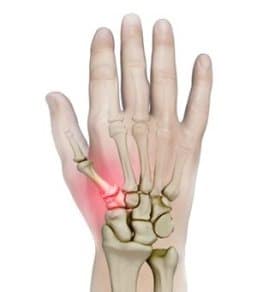

Wrist Scaphoid Fractures